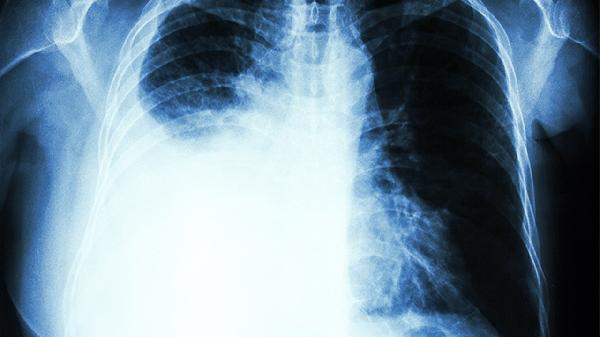

说到肺,很多人可能觉得它是个“沉默的器官”,平时不声不响,默默工作。但其实,肺也有自己的“语言”,只是我们常常忽略了它的“呐喊”。比如,当它不舒服的时候,可能会通过身体的其他部位来“喊疼”。今天,我们就来聊聊,肺不好的人,身上哪3处会“喊疼”。如果你没有这些症状,恭喜你,你的肺还算健康!

胸部疼痛是肺部问题的典型信号之一。当肺部出现炎症、感染或者肿瘤时,可能会直接刺激胸膜,导致胸部出现刺痛或钝痛。这种疼痛通常会在深呼吸、咳嗽或打喷嚏时加重,甚至可能伴随呼吸困难。需要注意的是,胸部疼痛并不一定都是心脏问题,肺部疾病同样可能引发类似症状。所以,如果出现不明原因的胸痛,尤其是伴随咳嗽、咳痰或发热时,一定要警惕肺部健康问题。

背部疼痛也可能是肺部问题的“信号灯”。肺部位于胸腔内,当肺部出现病变时,可能会通过神经反射引起背部疼痛。这种疼痛通常集中在背部的上半部分,尤其是肩胛骨附近。如果背部疼痛持续存在,并且伴随咳嗽、咳血或体重下降等症状,建议尽快就医,排查肺部疾病的可能性。